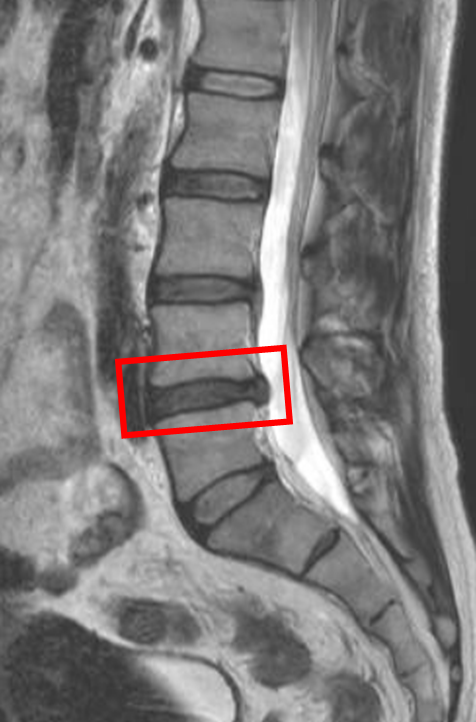

この患者様は赤い枠で示されている箇所(L4/5)に椎間板ヘルニアを認めます。